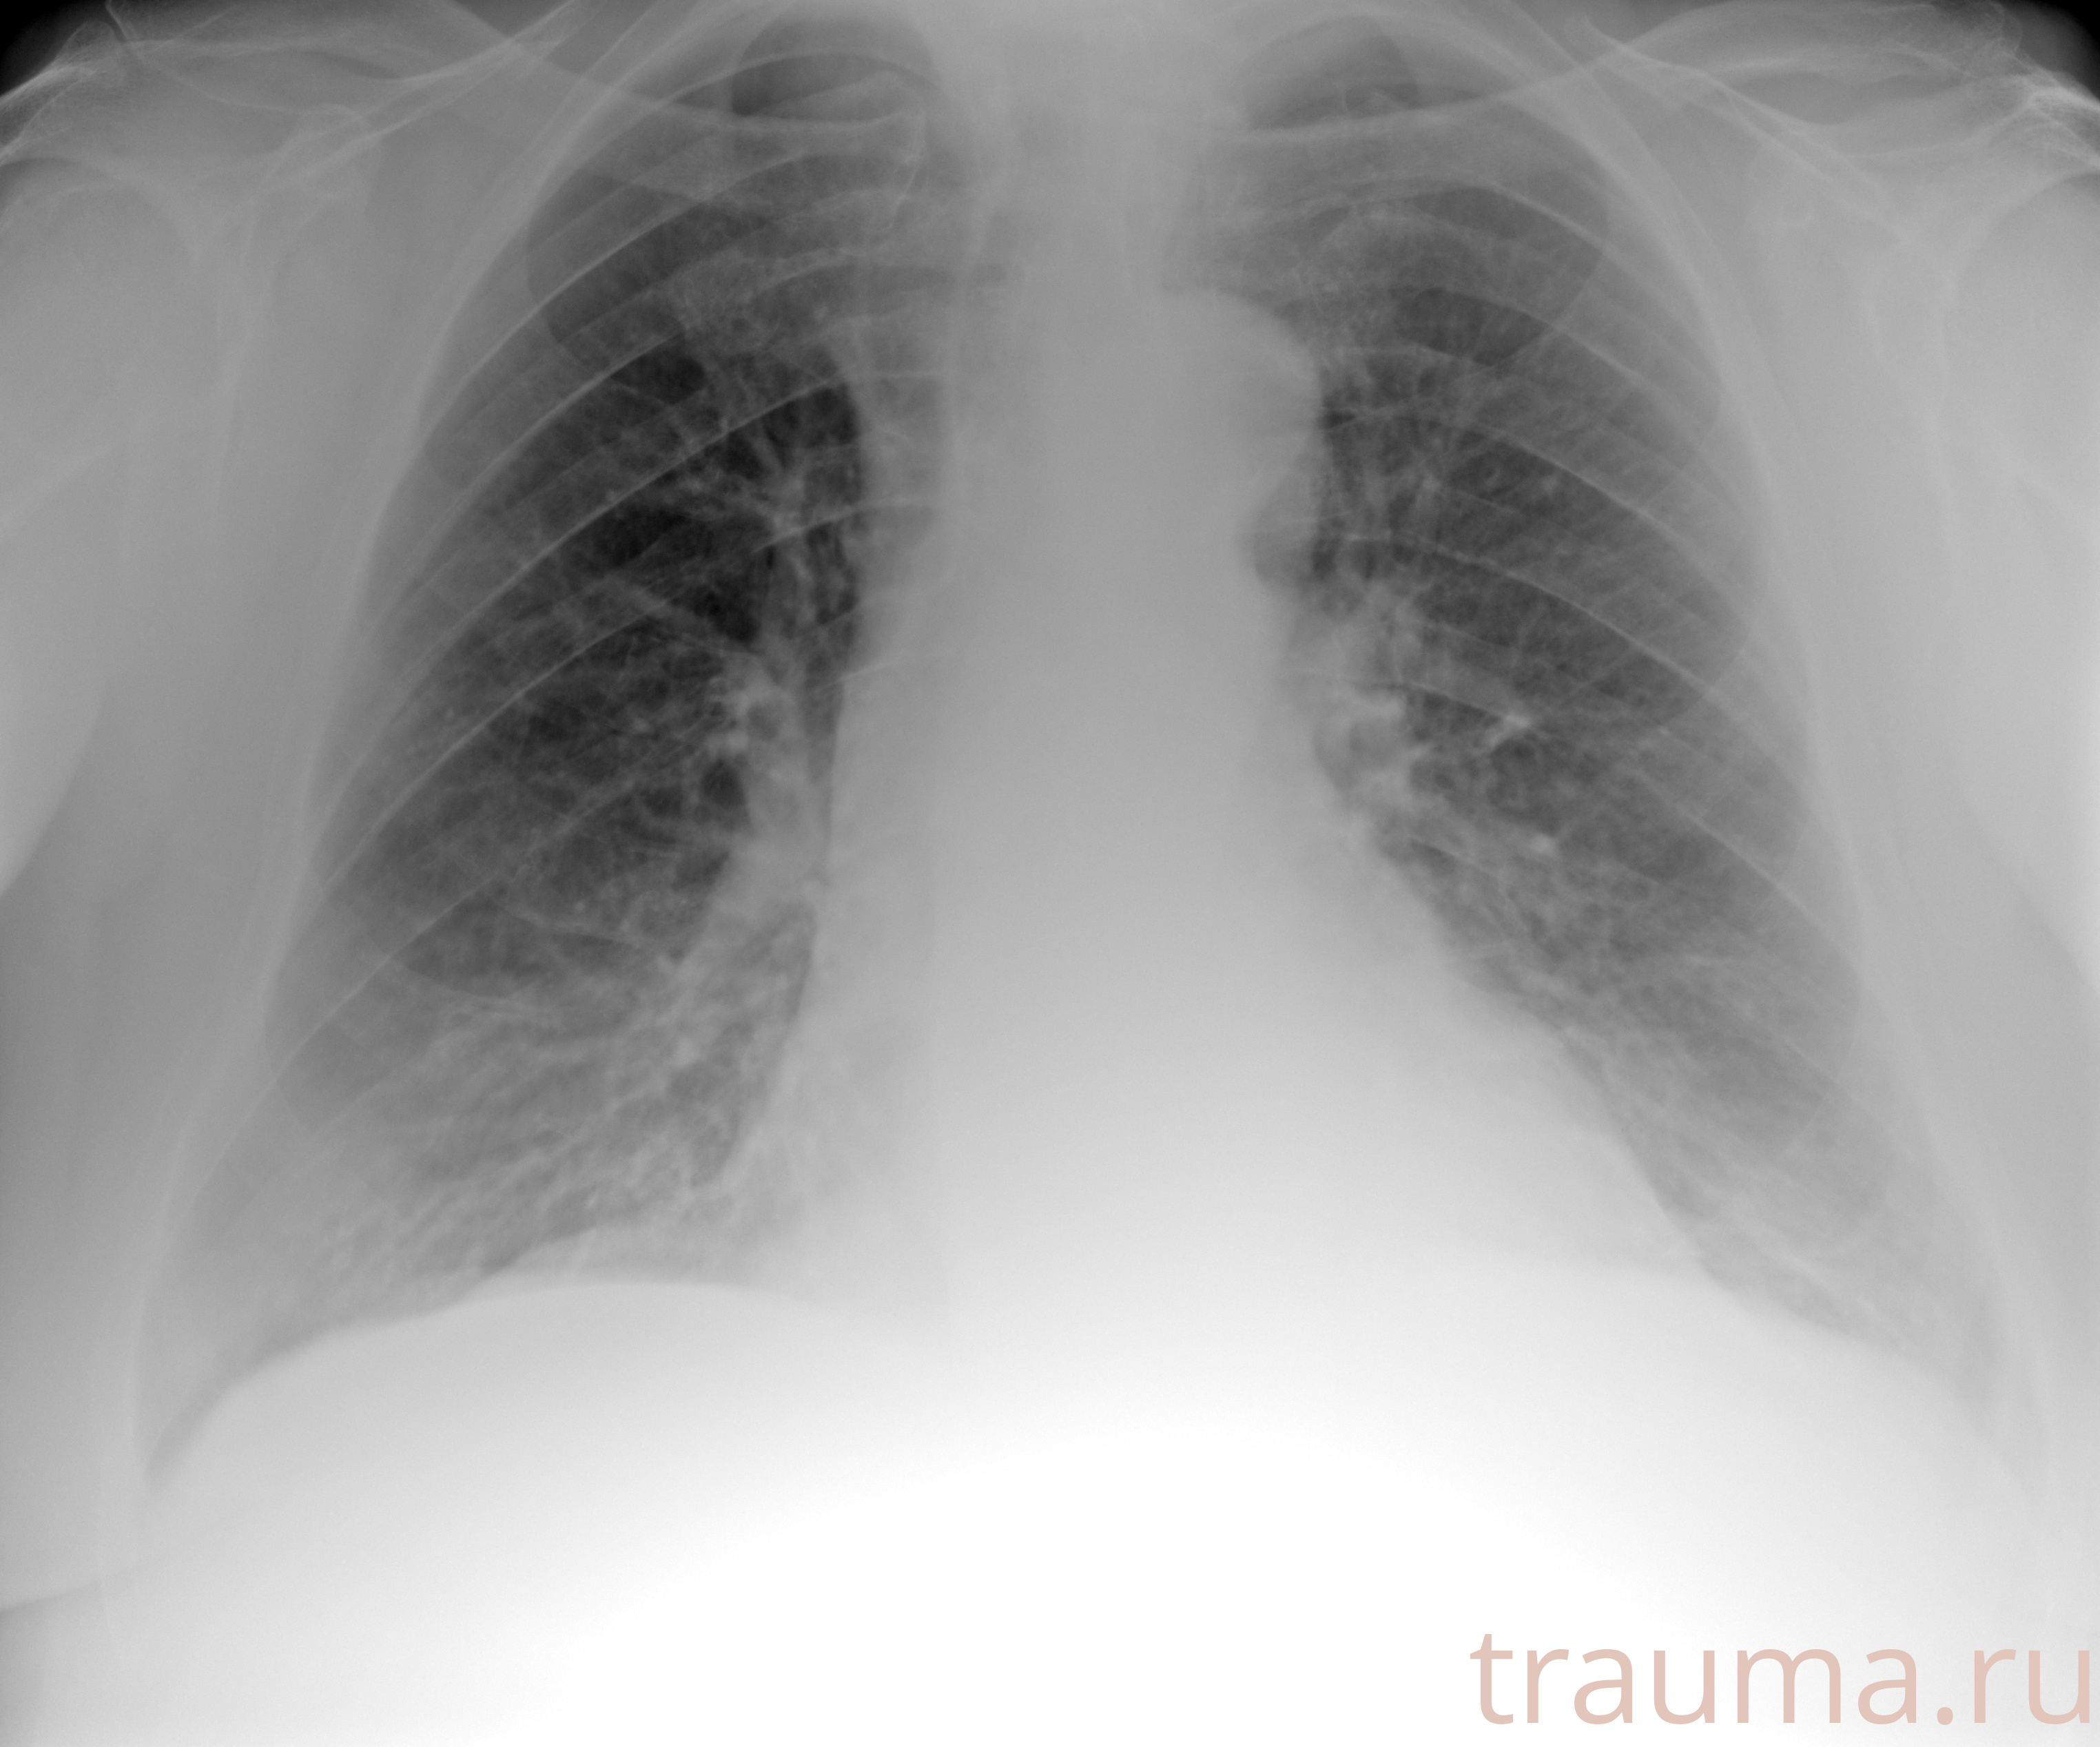

Рентгенограммы

Рентген на дому: по вашему адресу приезжает врач-рентгенолог, травматолог-ортопед с мобильным рентгеновским аппаратом, проводит диагностику травмы или заболевания, делает необходимые рентгенограммы, дает рекомендации по дальнейшему лечению. Получить качественные снимки в домашних условиях возможно благодаря уникальной методике, разработанной МосРентген Центром для института  Склифосовского

при переломе шейки бедра и пневмонии от компании МосРентген Центр - партнера Института имени Склифосовского